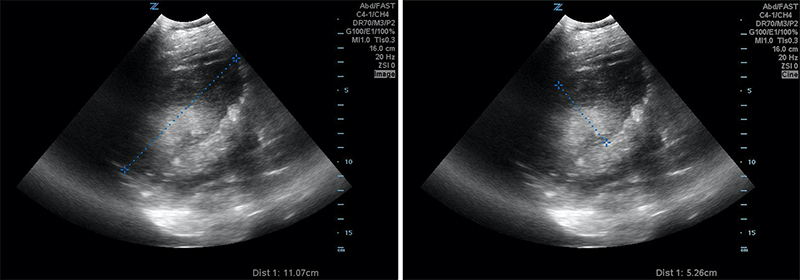

Figures 24B & 24C. Large pyogenic liver abscess with heterogenous material swirling inside the lesion, measuring >11cm in the long dimension (B) and >5cm in the shorter dimension (C).